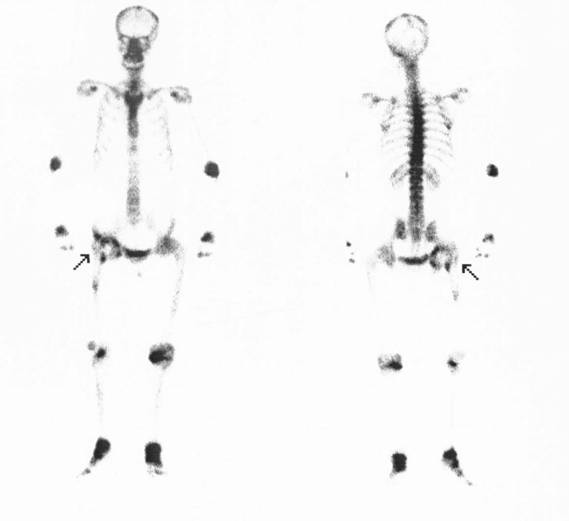

病例七:股骨头坏死

女性,33岁,因特发性血小板减少,长期服用类固醇激素治疗,近一个月来出现两侧髋关节酸痛。